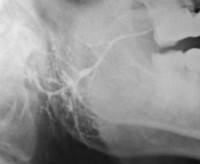

При проведении сиалометрического анализа снижение саливации наблюдается во время фазы выраженных проявлений. При паренхиматозной форме хронического сиаладенита с помощью сиалографии выявляют небольшие полости, заполненные контрастным веществом, просвет протоков сужен, контуры прослеживаются хорошо, паренхима не определяется. В случае интерстициального хронического сиаладенита на сиалограмме обнаруживают суженные протоки с неровными контурами. Паренхима железы не прослеживается. При сиалодохите устанавливается значительное расширение основного протока. В поздней фазе заболевания выявляют увеличенные в диаметре мелкие протоки. Хронический сиаладенит дифференцируют с острым сиаладенитом бактериальной и вирусной этиологии, доброкачественными и злокачественными новообразованиями железистой ткани, псевдопаротитом Герценберга, сиаладенозами. Пациента обследует стоматолог-хирург.